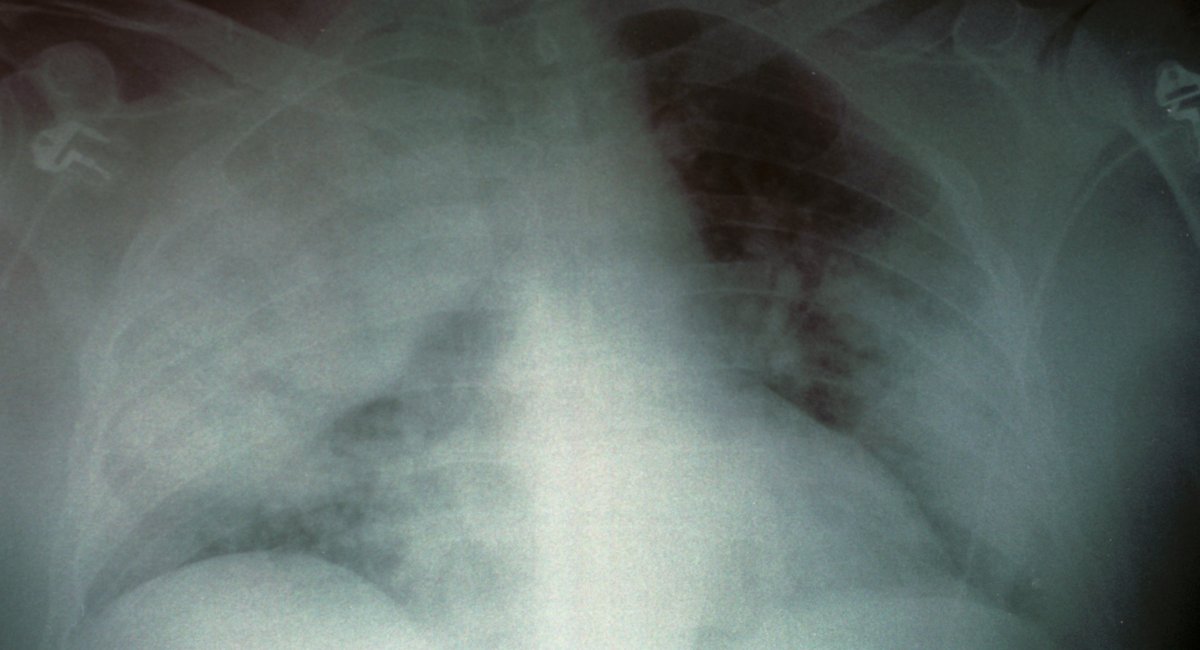

Legionnaires’ disease is a type of pneumonia that first emerged in Philadelphia during a convention in 1976, as noted by the U.S. Centers for Disease Control and Prevention.

The CDC clarifies that the disease isn’t transmitted between individuals. Instead, it usually spreads through inhaling mist that has Legionella bacteria, often found in systems like cooling towers, hot tubs, and plumbing. Legionella thrives in warm, stagnant water that lacks adequate disinfection.

Not everyone who encounters Legionella bacteria will show symptoms, and most individuals are at minimal risk of illness, according to city health officials. The symptoms mimic those of the flu and can encompass cough, fever, chills, muscle aches, and difficulty breathing. Additional symptoms might include headaches, fatigue, loss of appetite, confusion, or diarrhea.